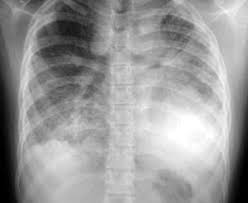

Cystic Fibrosis Pediatrics Msd Manual Professional Edition

Cystic Fibrosis Pediatrics Msd Manual Professional Edition from www.msdmanuals.com